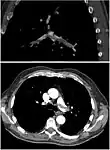

CT pulmonary angiography

CT pulmonary angiography (CTPA) is a pulmonary angiogram obtained using computed tomography (CT) with radiocontrast rather than right heart catheterization. Its advantages are that it is accurate, it is non-invasive, it is more often available, and it may identifying other lung disorders in case there is no pulmonary embolism. The accuracy and non-invasive nature of CTPA also make it advantageous for people who are pregnant.[58]

On CT scan, pulmonary emboli can be classified according to the level along the arterial tree.

Segmental and subsegmental pulmonary emboli on both sides

CT pulmonary angiography showing a "saddle embolus" at the bifurcation of the main pulmonary artery and thrombus burden in the lobar arteries on both sides.

Pulmonary embolism (white arrow) that has been long-standing and has caused a lung infarction (black arrow) seen as a reverse halo sign.

Assessing the accuracy of CT pulmonary angiography is hindered by the rapid changes in the number of rows of detectors available in multidetector CT (MDCT) machines.[59] According to a cohort study, single-slice spiral CT may help diagnose detection among people with suspected pulmonary embolism.[60] In this study, the sensitivity was 69% and specificity was 84%. In this study which had a prevalence of detection was 32%, the positive predictive value of 67.0% and negative predictive value of 85.2%. However, this study's results may be biased due to possible incorporation bias, since the CT scan was the final diagnostic tool in people with pulmonary embolism. The authors noted that a negative single slice CT scan is insufficient to rule out pulmonary embolism on its own. A separate study with a mixture of 4 slice and 16 slice scanners reported a sensitivity of 83% and a specificity of 96%, which means that it is a good test for ruling out a pulmonary embolism if it is not seen on imaging and that it is very good at confirming a pulmonary embolism is present if it is seen. This study noted that additional testing is necessary when the clinical probability is inconsistent with the imaging results.[61] CTPA is non-inferior to VQ scanning, and identifies more emboli (without necessarily improving the outcome) compared to VQ scanning.[62]